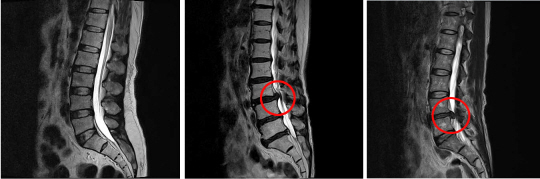

프로야구 한화 김성근 감독이 지난 어린이날 허리디스크 수술을 받고 회복 중이다. 김 감독은 이미 6년 전 허리디스크 수술을 받은 적이 있는데, 올 시즌을 앞둔 스프링캠프에서부터 재발해 통증에 시달렸지만 수술을 미루다가 긴급 수술을 받게 된 것이다. 김 감독 뿐 아니라 많은 디스크 환자가 수술을 미루다가 응급 상황이 닥친다. 반대로, 수술받았다가 효과를 보지 못하는 환자도 많다. 김 감독처럼 허리 디스크가 고질인 사람은 어떻게 대처하는 게 현명한 지 알아봤다.

일상생활에 불편이 커지면 시술이나 수술을 고려해야 한다. 잘 걷지 못할 정도로 증상이 심하거나 대소변 감각이 없어질 만큼의 중증이면 수술이 필수다. 이 정도 상태가 아니면, 다양한 치료법을 선택할 수 있다. 보존적 치료 다음 단계는 환부에 스테로이드 주사를 놓는 신경차단술 등의 시술을 고려할 수 있다. 이 시술은 건강보험 적용이 되지 않아 경제적 부담이 크며, 주사를 맞자마자 효과를 보는 환자도 많지만 효과가 나타나지 않는 경우도 꽤 있다. 마지막 단계가 수술인데, 허리디스크는 수술해서 정상 생활이 가능해져도 증상 자체는 약간 남거나 나중에 병이 재발하는 경우가 드물지 않다. 결국, 김성근 감독처럼 생활 불편과 통증을 참으면서 비수술적 치료법으로 관리하며 살 수도 있고, 재발 가능성을 감수하고라도 일단 완치를 노리고 수술을 시도할 수도 있다. 김재훈 원장은 "우리나라 장노년층은 허리에 칼을 대면 안된다는 선입견이 너무 강해 아예 병원에 오지 않는 디스크 환자가 많은데, 환자가 어떤 치료법을 선택하든 반드시 척추 전문의에게 진단받고 의사와 함께 결정해야 한다"고 말했다.